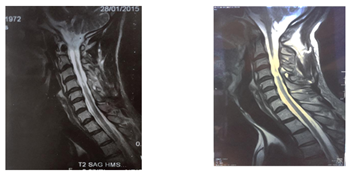

The first practitioner thought to peripheral nerve disorders and asked a lumbar scan and ENMG. The lumbar Scan performed showed degenerative osteoarthritis of the hinge lumbar without disco radicular conflict. ENMG was normal but Evoked Somesthesic Potential (PES) showed right S1 radiculopathy. After one month of unsuccessful treatments, the first cervical MRI is performed and showed one T2-weighted sagittal midline image with elevated signal within the cord at the C3-C4 level over a length of 30mm with the loss of cord volume. The T2-weighted axial image at the level of C3 demonstrates bilaterally symmetric well-circumscribed circular shaped foci with increased signal intensity. The appearance approximates the shape of a snake's eyes (Figures 1–3).

Figure 1 T1-weighted sagittal image with loss of cervical level C3-C4 cord volume - A) 2015 spinal cord MRI -B) 2017 spinal cord MRI.

Figure 2 T2-weighted sagittal midline image demonstrates elevated signal within the cord at the C3-C4 level over a length of 30mm with the loss of cord volume. - A) 2015 spinal cord MRI -B) 2017 spinal cord MRI.

He comes to neurology consultation in october 2017, given the persistence of pains and deficit despite the analgesic and anti-inflammatory treatments associated with physiotherapy. Clinical neurological examination shows a walking by mowing with the right lower limb. Non-proportional right hemiparesis more important on the lower limb. Bilateral hyperreflexia with bilateral Babinski and Hoffman signs, bilateral amyotrophy of the proximal muscles, tactile hypoesthesia in the right hemibody, algesic hypoesthesia in the left hemibody, no vibration and position sense perception, a sensory ataxia and no cranial nerves disorders. The new spinal cord MRI performed in 2017 shows the same images in cervical level with more atrophy (Figures 1–3). Brain MRI is normal. The blood cell count shows WBC:4, 2g/L, Hemoglobin:13,9g/100ml, MCV:92μ3, Platelet:264g/l ; Blood erythrocyte sedimentation rate (1H):4mm; C-Reactive protein:0,4mg/l; Negatif human immuno-deficiency virus test.